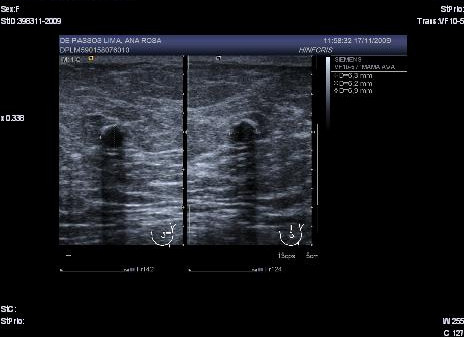

An eighty-one year old patient consulted for an emerging nodule in the right breast without any family or personal history of interest. On physical examination, the patient had a nodule of 20 mm in the lower inner quadrant of the right breast. In the mammogram a nodular image was observed that with ultrasonography was identified as a cyst containing clear borders and good sound transmission (Fig. 3): the FNA evidenced papillary epithelial proliferation.

Figure 3

Cyst with content with clearly defined borders